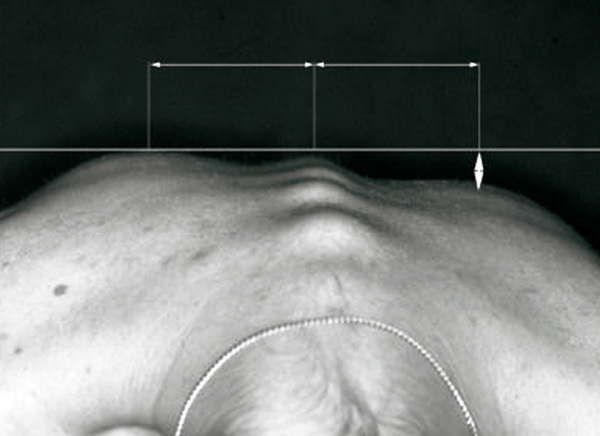

Cette anomalie des courbures dorsales est le signe clinique pathognomonique d'une scoliose. La gibbosité se démasque lorsque le patient se penche en avant, les genoux restant en rectitude.